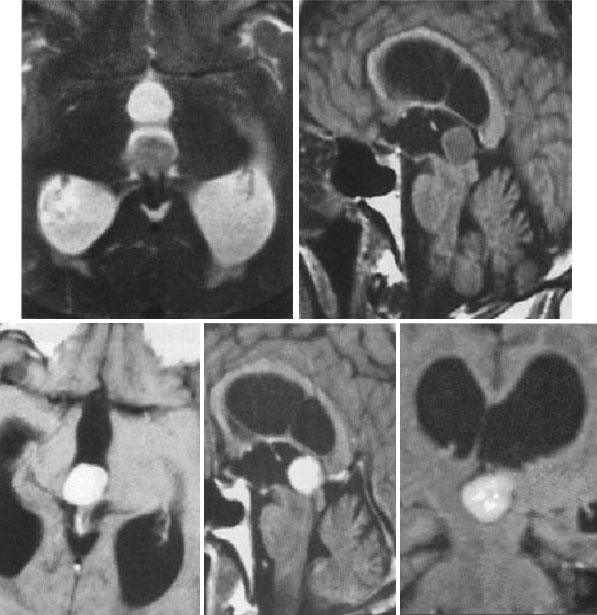

Опухоль шишковидной железы (пинеацитома) на МРТ